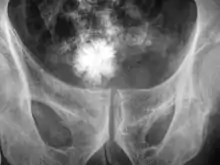

La taille des calculs varie d'un grain de sable à celle d'une balle de golf. Les plus gros, dits « coralliformes », moulent l'intérieur du rein, ayant ainsi l'aspect de branches de corail. Les calculs sont généralement évacués par miction.

Le calcium relativement dense rend ces calculs radio-opaques et ils peuvent être détectés par radiographie de l'abdomen. L'échographie, le scanner et la radiographie numérisée sont les examens de diagnostic les plus précis pour la détection des calculs.

- la radiographie simple ou avec tomographies montre les calculs radio-opaques en projection des voies urinaires ;